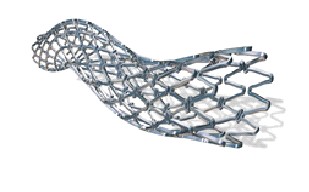

Стенты коронарные

В данную подсубпозицию включаются стенты коронарные, предназначенные для помещения внутрь пораженной части коронарного сосуда, где, расширяясь за счет эффекта «памяти» материала изготовления или с помощью баллона, выполняют функцию опорного каркаса для укрепления и поддержания стенок пораженного участка сосуда, обеспечивая нормальный кровоток по сосуду и нормальное кровоснабжение органа. Такие стенты могут быть изготовлены, например, в виде тонкой полой металлической или полимерной трубки

с ячейками либо из цельной круглой проволоки, которой сначала придается синусоидальная форма, а затем проводится спайка непрерывной синусоидальной конструкции. |

Примеры изображения стентов приведены ниже.